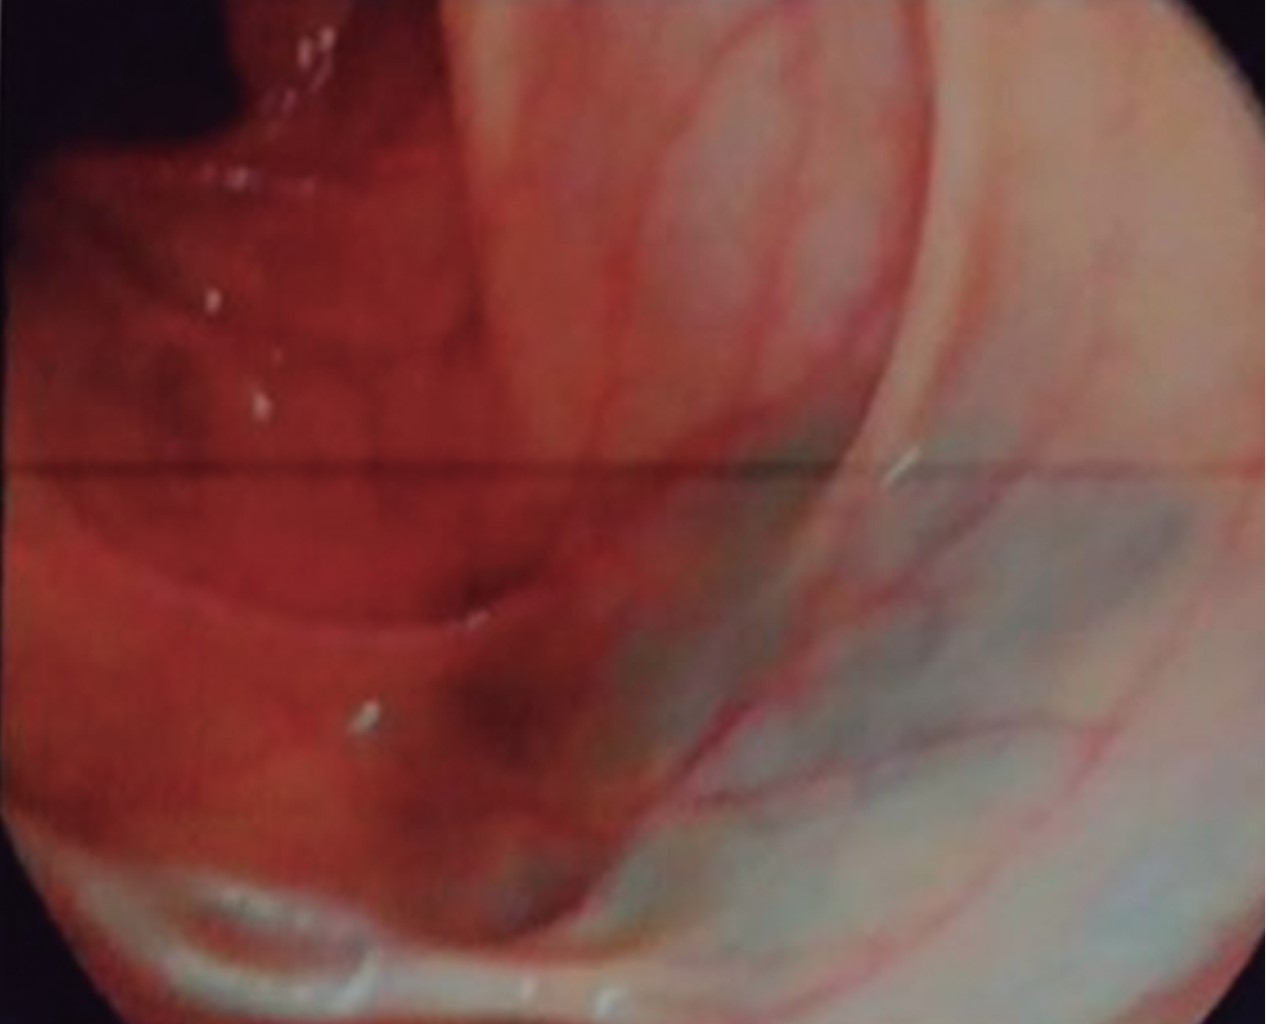

An abdominal ultrasonography (USG) scan was performed, reporting an image of a tumor in the right iliac fossa measuring 10.5 × 5.5 × 9.9 cm. The colonoscopy study showed no evidence of tumor in the rectum and colon, and an apparent extrinsic compression at the ileocecal valve orifice (Figure 1).

Figure 1